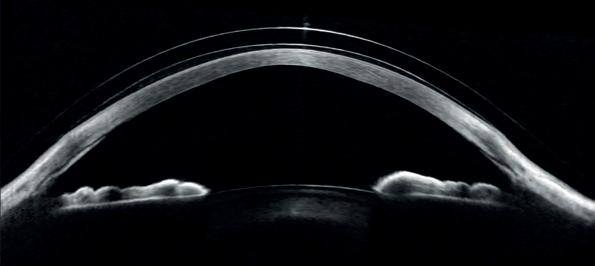

An Australian study has shown that cataract surgery using multifocal intraocular lenses (mfIOLs) can achieve good outcomes for patients and be cost-effective in a public hospital setting.

Cataract surgery is a safe and effective procedure that is performed in both the private and public sectors, and advances in lens technology now offer the possibility of multifocality.

However, mfIOLs are not readily available in the public sector, due to the complexity of patient selection and of trainee experience with them.

A study at Sydney’s Westmead Hospital showed it was possible to develop a trainee-led selection pathway that ensures the cost-effectiveness of mfIOL implantation within the government funded health system.

As part of the single-surgeon prospective cohort study, 54 eyes from 27 patients underwent cataract surgery with mfIOL implantation.

The study evaluated outcomes including the resultant visual acuity, the experience of visual disturbances, dependence on glasses and patient satisfaction.

They also performed a cost analysis.

Multifocal IOLs are not available in the public system for various reasons.Image: arren Schere/ Shutterstock.com.

most patients achieved excellent visual outcomes with mfIOLs, with high satisfaction rates reported".

“Around 85% were able to see well without glasses at a distance, 81% at intermediate distances, and 59% at near distances.”

It said the conclusion was that the additional cost of mfIOLs was comparable to the cost of glasses over time, making them a cost-effective option.

“In conclusion, the study demonstrated that the selection pathway effectively addressed challenges in choosing patients for mfIOLs in public hospitals, which can facilitate access to mfIOLs for public patients.”